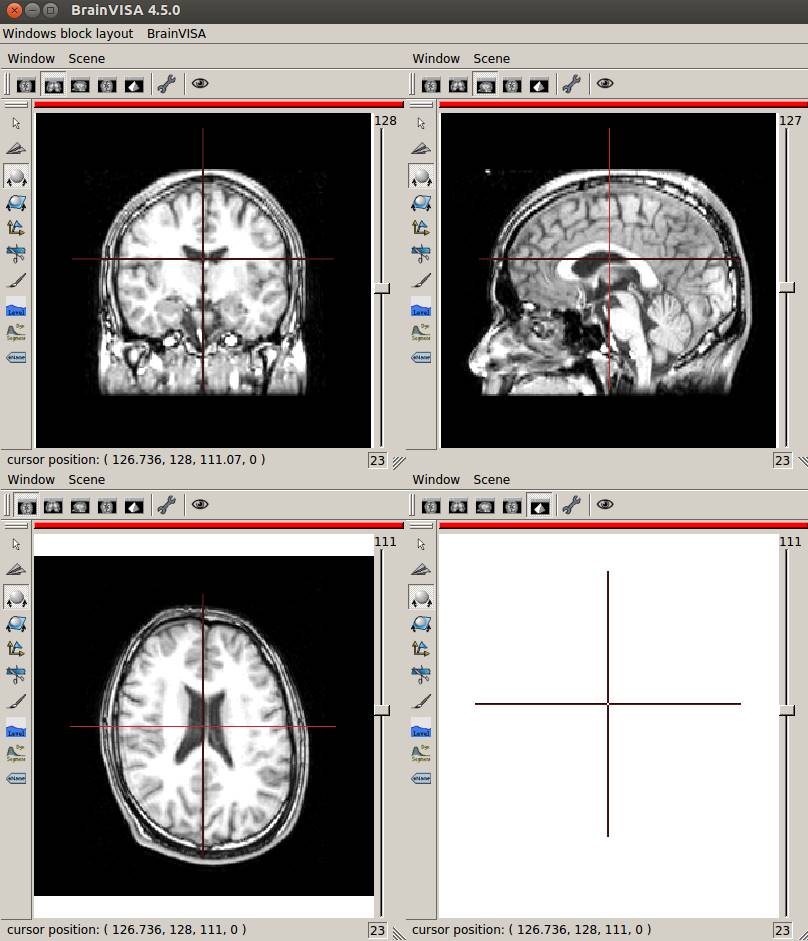

Windows→Open a 4 views blockをクリックします。

3断面で表示させてみました。